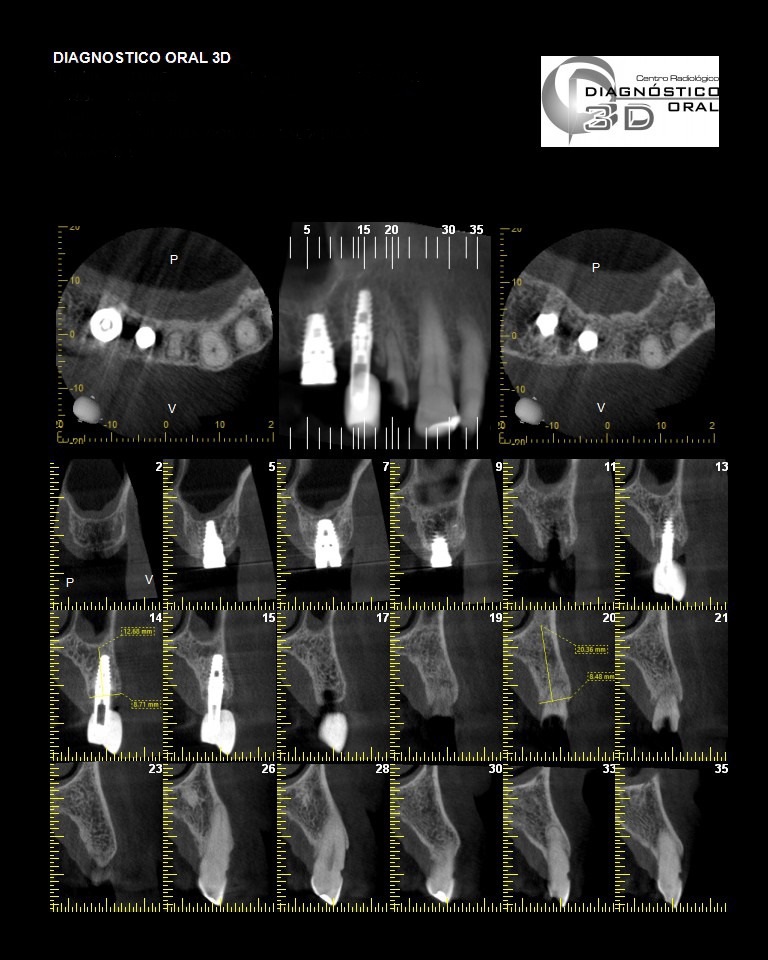

El Centro Radiológico Diagnóstico Oral 3D, es una empresa antioqueña que ofrece a sus pacientes desde el año 2009, tecnología de vanguardia en radiografías tridimensionales con calidad fotográfica. Las posibilidades para mejorar la eficacia en los diagnósticos bucales son evidentes, también lo son las posibilidades de manipulación de imagen. El sistema de imágenes en 3D ofrece detalles sin precedentes, convirtiéndola en la opción idónea para la mayoría de aplicaciones odontológicas, incluyendo implantes, tratamiento de conductos, ortodoncia, odontopediatría, periodoncia y cirugía

El mayor beneficiado con el uso de esta tecnología es el paciente, el cual podrá ser evaluado en todas sus dimensiones con una baja dosis de radiación, con un costo accesible y sin contaminar  el medio ambiente. Dependiendo de la necesidad del paciente, hay varios tipos de tomografías y los especialistas en el área odontológica hacen uso de ellas según su especialidad.

La radiología oral especializada es fundamental para una práctica dental integral, proporcionando información específica que influye en la toma de decisiones clínicas y mejora los resultados del tratamiento para los pacientes

Implantología dental